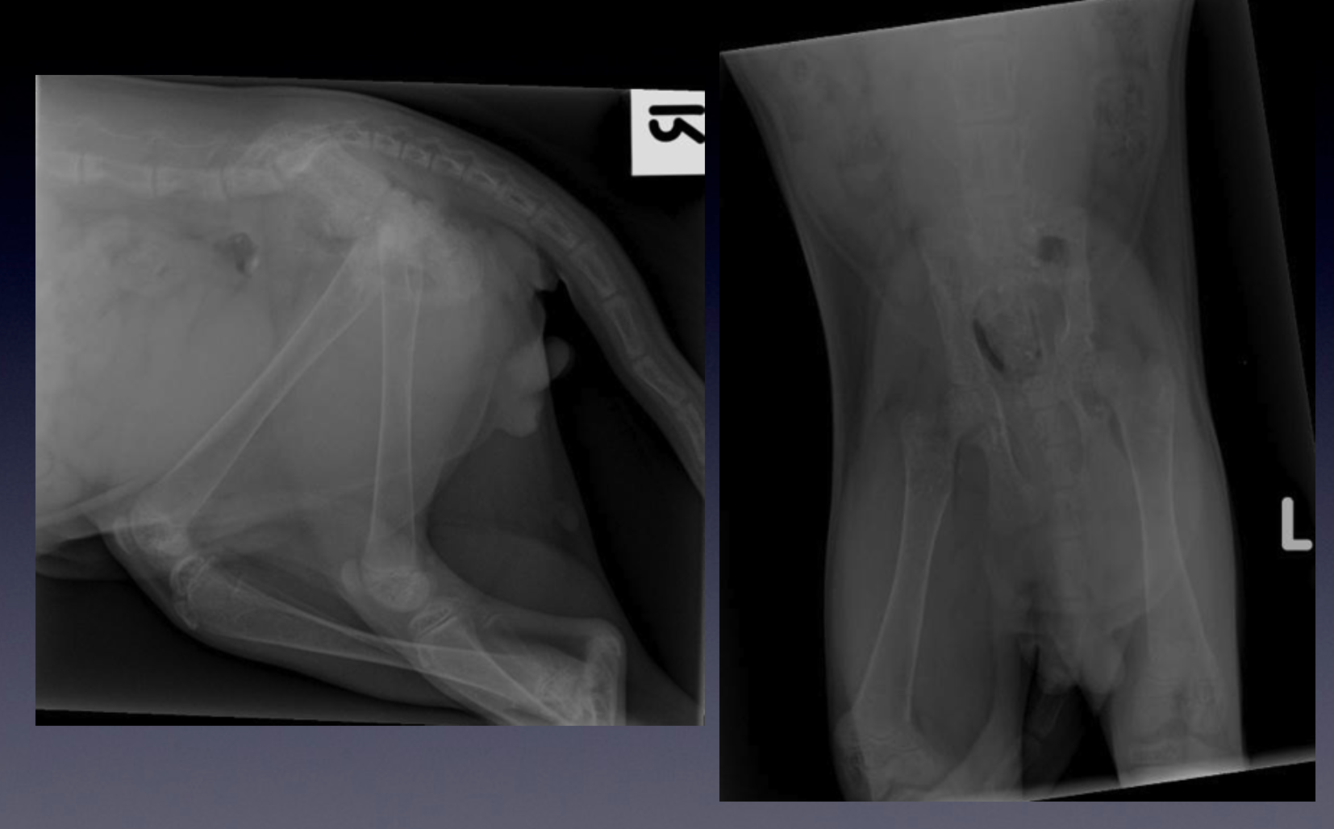

Patient number 245702 - Normal Feline Pelvis

WHAT VIEWS ARE THESE?

Use the same criteria for evaluation as in dogs.

Compare these radiographs to the canine pelvis.

•

Notice the difference in the shape of the bones between the two species, with the feline long bones

being straighter than the canine bones.

Feline vertebral bodies are longer and narrower when compared to canine vertebral bodies.

Make sure you can recognise the difference between the two species, based on the radiographic

appearance.

Did you notice the smooth solid bone ventral to and bridging L5-6 vertebral bodies? This is called ventral

vertebral spondylosis. Although this is not a normal finding, the smooth and solid nature of the bone

indicates this is an inactive process, and may be an incidental finding without any clinical significance.

Lateral and ventrodorsal (VD) hip extended projection.

Case 8: Patient 239099

SPECIES? VIEW?

Consider patient positioning; is positioning adequate or do you have to repeat the radiograph?

How old is this cat? How can you judge the age of an animal?

Compare this radiograph to the normal feline pelvis.

Please identify the following:

thin cortices of the long bones

generally poor mineralisation of the skeleton

deformed shape of the lumbosacral area on the lateral projection

folding fracture of the left ileum

This cat has a polyostotic osteoporotic disease, therefore the disease must be systemic. Most

systemic diseases affecting the skeleton are of metabolic origin - the ‘metabolic bone

diseases’. This cat was on a meat only diet and has nutritional secondary

hyperparathyroidism, which develops secondary to a calcium-posphorous imbalance in the

food. Dietary calcium deficiency cases a decrease in serum calcium, which triggers an

increase in PTH secretion and induces bone resorption from the skeleton, causing diffuse

osteoporosis.

Lateral and ventrodorsal legs extended projections of the pelvis of a cat.